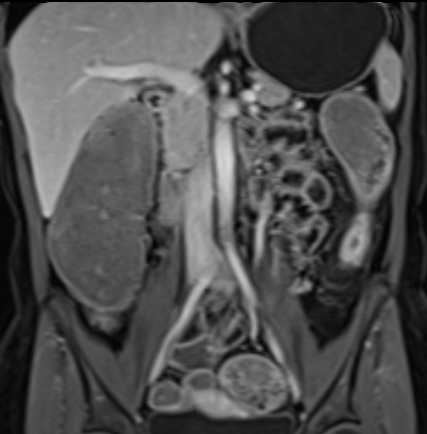

Bệnh nhân nữ 48 tuổi, đang điều trị bằng thuốc kháng TNF, được chỉ định nội soi đại tràng.

Phát hiện hẹp lòng ruột ở đại tràng sigma, không thể vượt qua được khi nội soi.

MR-enterography được thực hiện để đánh giá mức độ lan rộng của chỗ hẹp.

Cuộn qua các hình ảnh.

Ruột non bình thường, nhưng ghi nhận các đoạn hẹp ở đại tràng xuống và đại tràng ngang.

Cả hai đoạn hẹp đều có thành ruột dày đến 8 mm và ngấm thuốc rõ rệt theo kiểu niêm mạc ở đại tràng xuống và kiểu phân lớp ở đại tràng ngang.

Giãn ruột trước chỗ hẹp được ghi nhận ở cả hai đoạn.

Do các chỗ hẹp này không hiện diện khi nội soi đại tràng trước khi điều trị kháng TNF, nhiều khả năng chúng đã hình thành trong quá trình điều trị.

Do đó, quyết định phẫu thuật cắt đại tràng gần toàn bộ với miệng nối hồi-sigma đã được đưa ra.